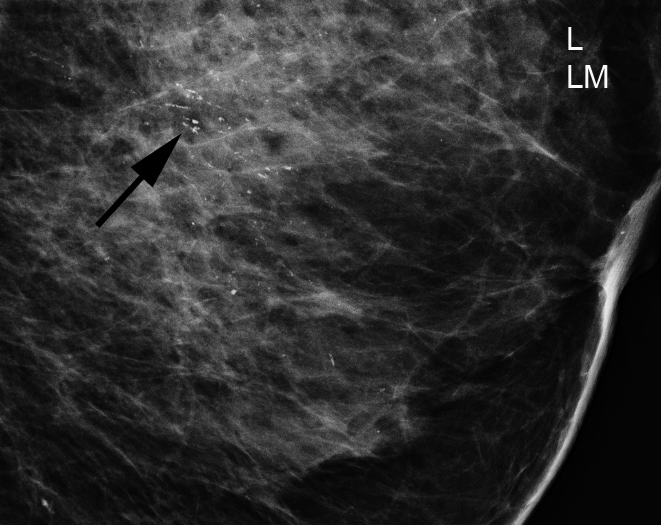

With help from the North Rhine-Westphalian State Cancer Registry, evaluations were made of 53,375 examinations from the implementation phase of the screening, focusing on the detection of breast cancer in the screening process and at the end of the biennial interval after screenings in which nothing was detected. From these data, detection rates through early detection mammography screening were established for invasive breast cancer, as well as during the subsequent biennial interval. Based on immunohistochemical examinations, the determination of hormone receptors and the HER2/neu status, subtypes were created with respect to tumour aggressiveness: HER2 positive and triple negative breast carcinomas were defined as being aggressive.

A detailed analysis of aggressive breast cancer among hormone receptor negative and HER2 positive carcinomas shows detection rates which are six times higher – and among triple negative carcinomas twice as high – in the screening than after the biennial interval. Aggressive invasive breast carcinomas have the highest rate of diagnosis in screening among women in the 60-69 age group. The stage distribution of aggressive invasive breast carcinomas is better than after the interval.